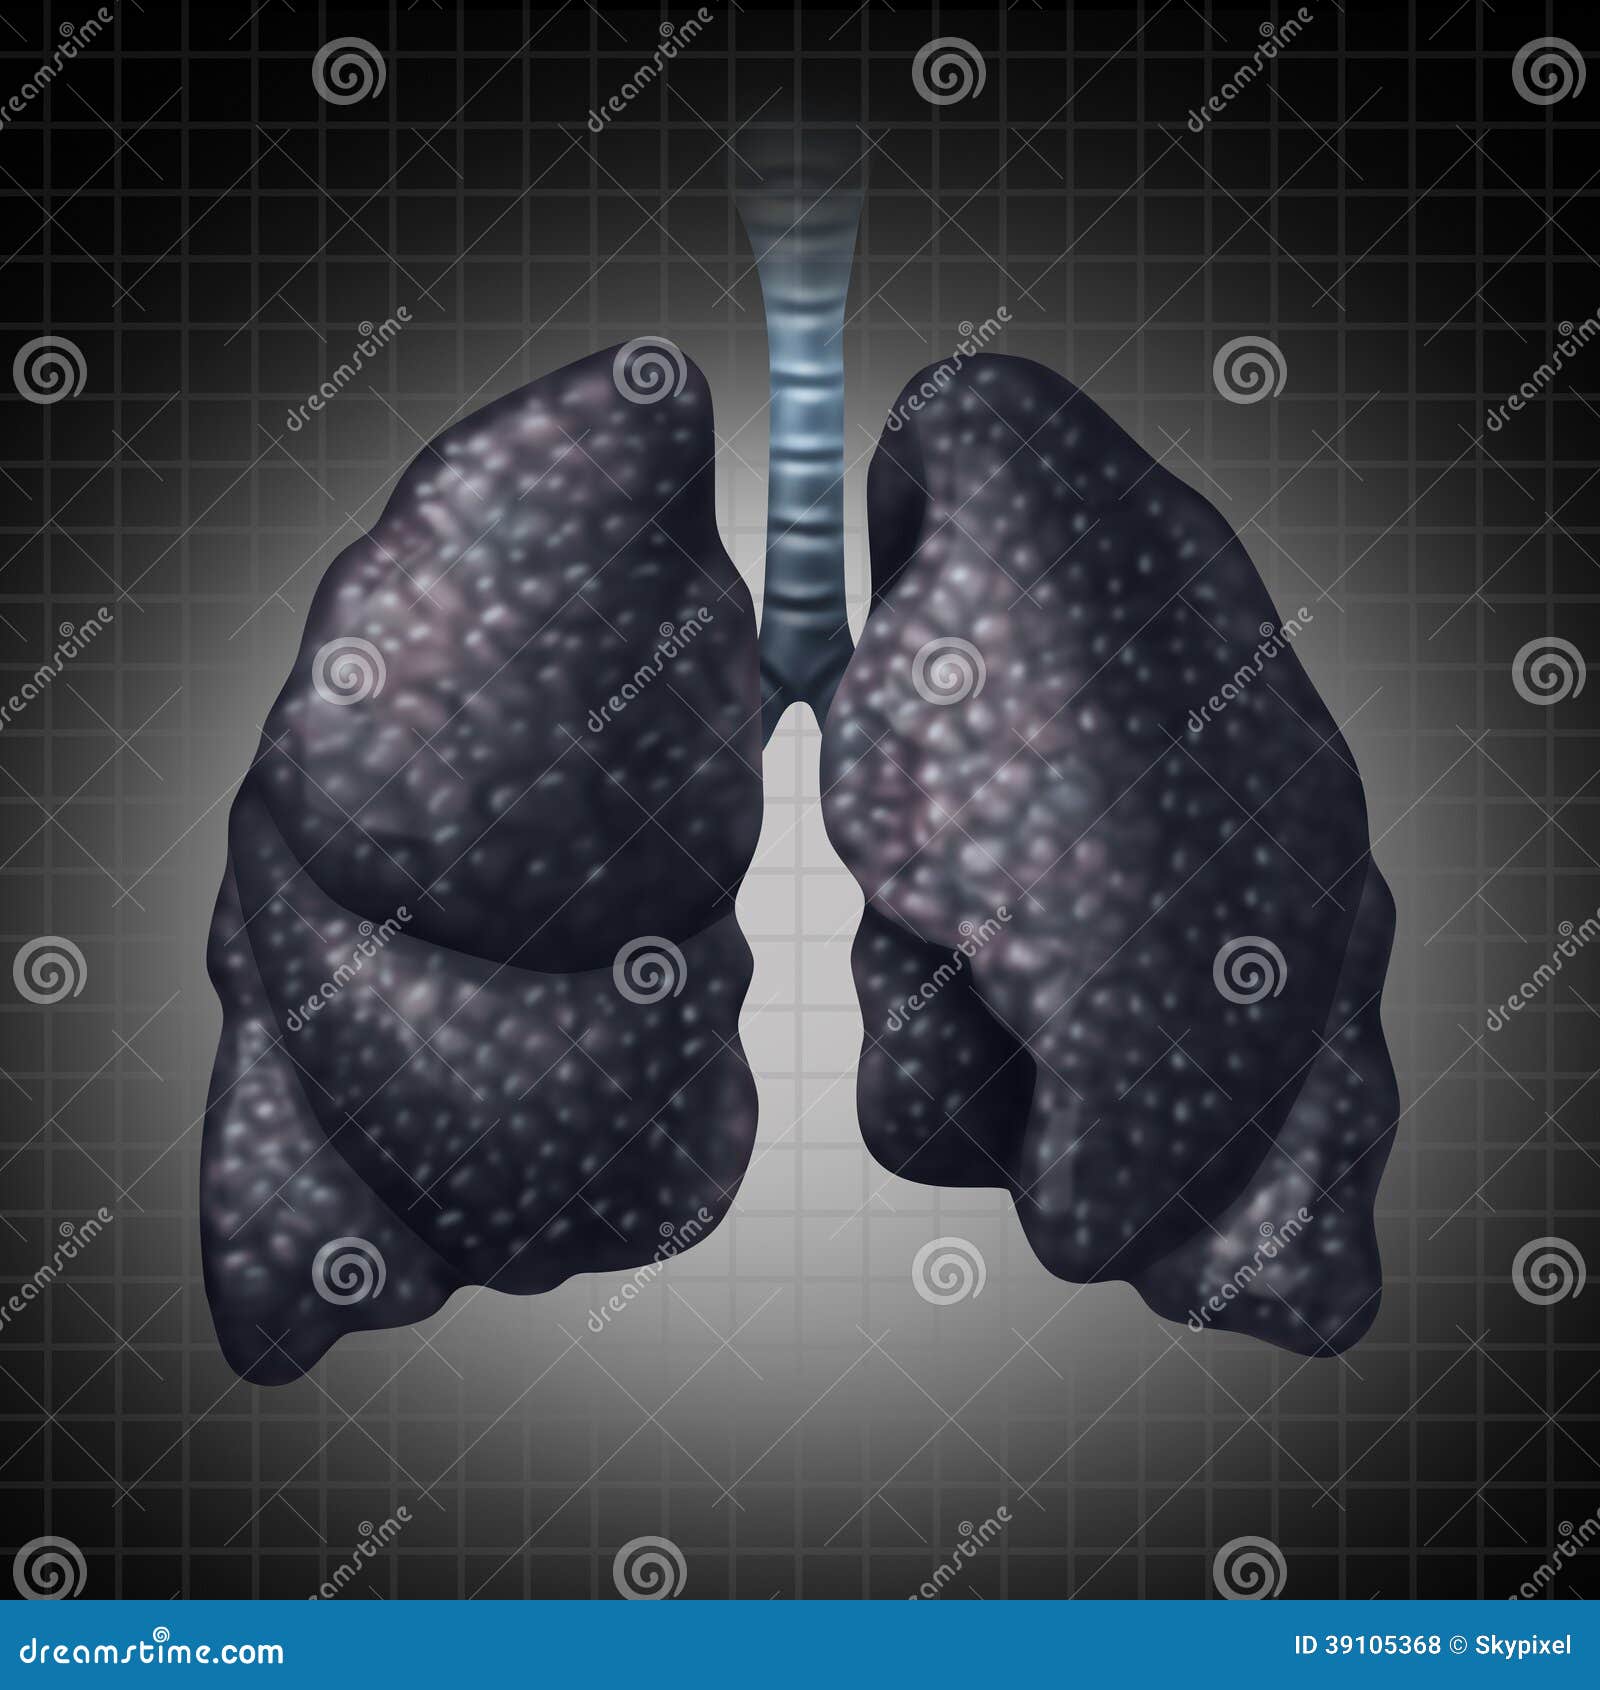

Обои для телефона с изображением лёгких человека